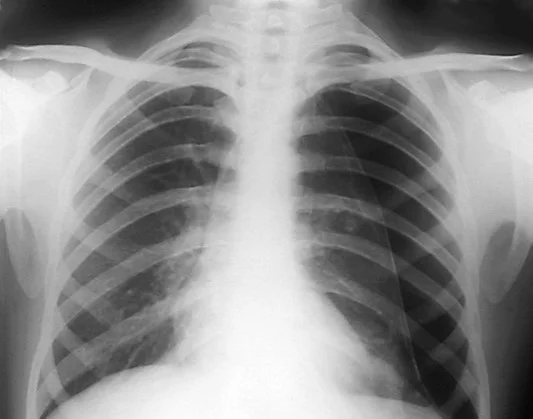

The Kirkpatrick article attempted to define the test characteristics of bedside thoracic ultrasound as performed by trauma surgeons (training and experience not explained) on blunt and penetrating trauma patients. The study demonstrated a higher sensitivity for EFAST compared to CXR (49% vs. 21%), but overall reported a lower sensitivity for EFAST than the Wilkerson paper.

The Wilkerson article was a literature review of the sensitivity of bedside thoracic ultrasound vs. a single supine chest x-ray for the detection of pneumothorax in blunt trauma patients that included 4 prospective observational studies. This study found a much higher sensitivity of ultrasound (sensitivity 86-98% with a specificity 97-100% compared to CXR with sensitivity 28-75% and specificity 100%) than the Kirkpatrick article. The images in this study were done by EM physicians and we surmised that this may have been due to more experienced operators given that the studies occurred many years later.